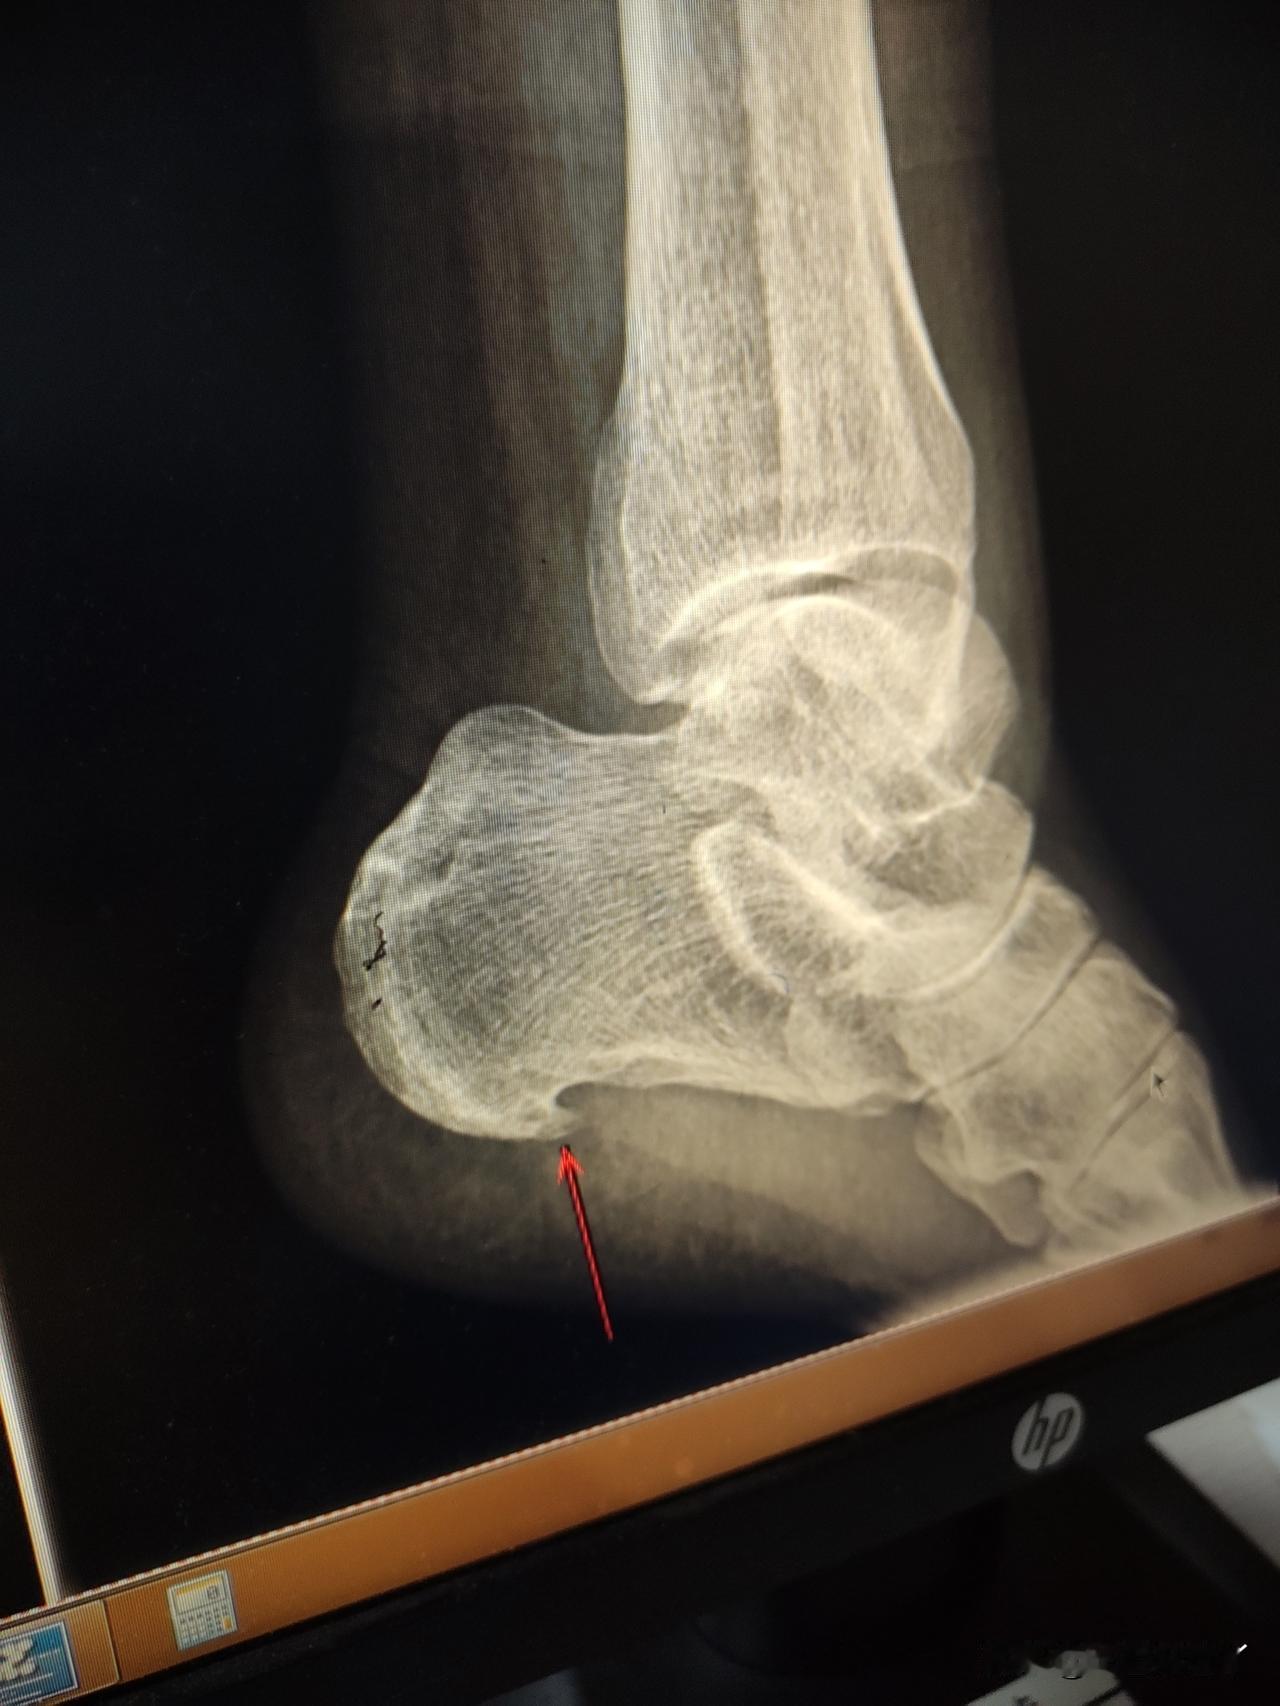

脚后跟疼,做了一个DR平扫。

下午去医院拿报告,麻团儿要陪我去,我没让他去,我说

昨天做DR平扫,脚后跟不是有好大一个骨刺嘛,豆包建

等待的空挡儿,我挂了个骨科看看我的脚后跟为啥疼。

脚后跟有